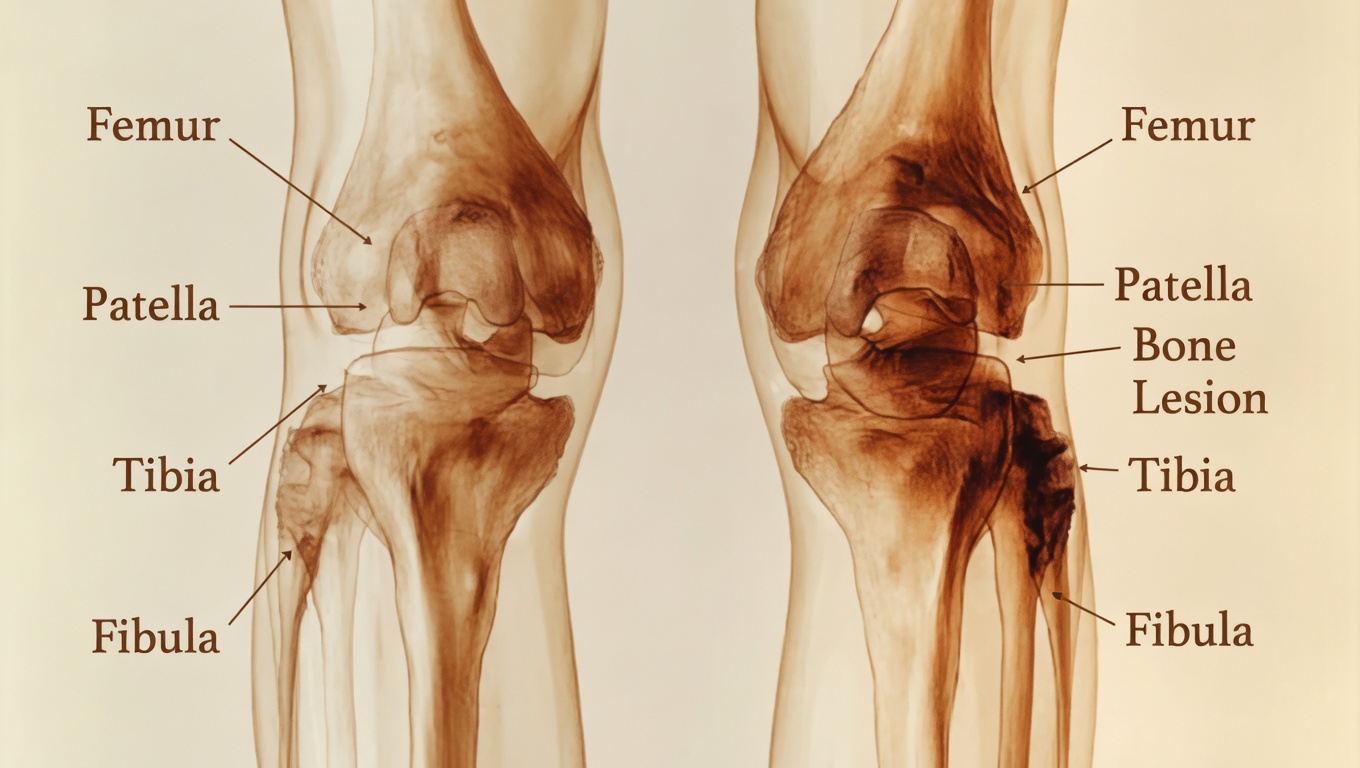

Vitamin D is often known as the “sunshine vitamin,” but its role goes far beyond sunlight exposure. It helps the body absorb calcium, which is essential for maintaining bone strength and structure. Medical research has consistently linked low vitamin D levels with a greater chance of bone pain and muscle discomfort, especially in the lower body.

There is another important piece to this. Muscles depend on vitamin D to help regulate contraction and support a balanced inflammatory response. When the body does not have enough, the result may be the familiar aching feeling that often settles in the knees, shins, calves, or ankles. Reviews and guidance from respected institutions such as Cleveland Clinic and Yale Medicine also emphasize that vitamin D influences both skeletal strength and everyday physical comfort.

Lifestyle changes can be helpful, but ongoing pain should not be ignored. If your leg or bone discomfort continues despite making adjustments, or if you also notice swelling, redness, or sudden difficulty moving, it is a good idea to contact your doctor.

A healthcare provider can order a simple blood test to check your vitamin D level and look for other possible causes of your symptoms. That kind of personalized evaluation can save time and reduce guesswork.